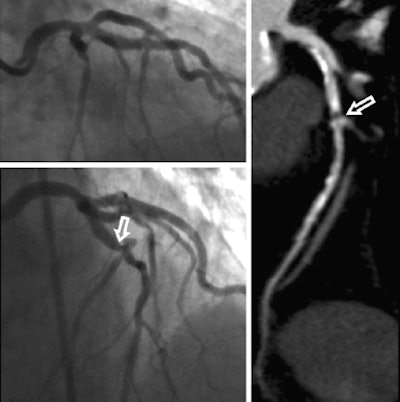

The researchers from MUSC and the University of Frankfurt prospectively compared the per-segment and per-patient accuracy of coronary CTA and invasive coronary angiography (ICA) for diagnosing significant stenosis using composite findings from both tests as an enhanced reference standard.

Using the enhanced reference standard instead of the initial angiography interpretation alone, accuracy of coronary CTA for identifying segments (patients) with 50% or greater stenosis increased from 97.7% (96.5%) to 98.1% (98.2%).

Per-segment/per-patient sensitivity rose from 90.5% (100%) to 90.8% (100%), and per-segment/per-patient specificity increased from 98.4% (94.3%) to 98.9% (97.1%).

Using the enhanced referenced standard shows that "these two tests are not that much different," Schoepf said. The results convey a couple of messages about the tests, he said.